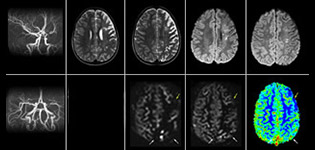

pCASL hilft bei der Abklärung der zerebralen Perfusion ohne Kontrastmittel

Pseudo-continuous Arterial Spin Labeling (pCASL, pseudo-kontinuierliche Spinmarkierung) wurde für die Bildgebung der zerebralen Perfusion ohne Kontrastmittel entwickelt. „Dies ist bei Kindern sehr erstrebenswert, da bei ihnen grundsätzlich versucht wird, die Gabe von Kontrastmittel weitestgehend einzuschränken“, erläutert Dr. Miller. Zunehmende Sicherheit bei spezifischen Anwendungen „Die Zuverlässigkeit von pCASL sicherten wir über einen Vergleich mit kontrastmittelbasierter Bildgebung ab. Nachdem wir uns davon überzeugt hatten, dass mit beiden Verfahren dasselbe dargestellt wurde, vergrößerten wir unsere Diagnosesicherheit noch über eine serielle Bildgebung im akuten Stadium bzw. in den langfristigen Stadien bei einer Anzahl von Patienten mit arteriellen Veränderungen.

Dr. Miller verwendet pCASL bei allen Patienten mit chronischen und akuten zerebrovaskulären Befunden wie akutem Schlaganfall sowie Patienten mit Anzeichen einer akuten Entzündung im Gehirn und gelegentlich bei Patienten mit Tumoren für eine Perfusionsbewertung des Tumors.

„In Kombination mit diffusionsgewichteter Bildgebung kann dieses Verfahren zu einer detaillierteren Beurteilung des Grades der Perfusionsstörung bei Patienten mit akuter Ischämie beitragen. Wir haben eine Reihe von Patienten, die unter chronischer arterieller Insuffizienz aufgrund früherer arterieller Störungen oder erworbenen arteriellen Veränderungen wie Sichelzellenanämie oder Neurofibromatose leiden. Gelegentlich manifestiert sich ein Krankheitsfortschritt beim Kind zunächst in einer reduzierten zerebralen Perfusion, bevor Schlaganfallsymptome klinisch oder in der diffusionsgewichteten Bildgebung manifest werden. Wir nutzen pCASL zur Unterstützung bei der Abgrenzung von Perfusionsstörungen.“

Anderen neuen Benutzern würde ich ebenfalls empfehlen, mit der Befundung von pCASL-Bildern im Vergleich zu anderen Standardbildgebungsverfahren zu beginnen – T2 und FLAIR und DWI –, bis sie selbst Sicherheit bei der Auswertung dieser Bilder gewinnen.“ „Der Nutzen von pCASL wird insbesondere bei Patienten mit chronischer zerebrovaskulärer Stenose deutlich, wo das Klinikteam Aufschluss darüber benötigt, wie die kompensatorischen Mechanismen des Gehirns wirken, um dessen ordnungsgemäße Durchblutung sicherzustellen. Das Klinikteam bezieht diese Funktionsweise der kompensatorischen Mechanismen häufig in die Entscheidung ein, ob ein chirurgischer Eingriff durchgeführt oder andere Maßnahmen ergriffen werden.“ „Eine weitere spezielle Anwendung besteht in der Beurteilung der zerebrovaskulären Reaktivität mit einer Diamox Perfusionsuntersuchung, bei der wir zwei Sätze mit pCASL-Bildern subtrahieren.“

Mit pCASL erzielte Effizienzsteigerungen

„pCASL ist mittlerweile zu unserem bevorzugten Untersuchungsverfahren für die Perfusionsbewertung geworden und hat die DSC-basierte Perfusionsbildgebung mit Kontrastmittel hier abgelöst. Bei Patienten, für die kein Kontrastmittel vorgesehen war, können wir pCASL für die Perfusionsbildgebung durchführen, ohne die Untersuchung stoppen zu müssen. Der Patient wird einfach herausgeschoben und ein Zugang gelegt. Auch die Nachbearbeitung, die bei Kontrastmitteln mit dynamischer Suszeptibilität nötig ist, entfällt. Außerdem ist es möglich, eine Perfusionsbildgebung beim selben Patienten während einer Untersuchungssitzung zu wiederholen, was in Fällen, wo sich der Patient bewegt bzw. in Situationen hilfreich ist, wo ein Scan vor der pharmakologischen Perfusionsbildgebung erfolgen muss.“